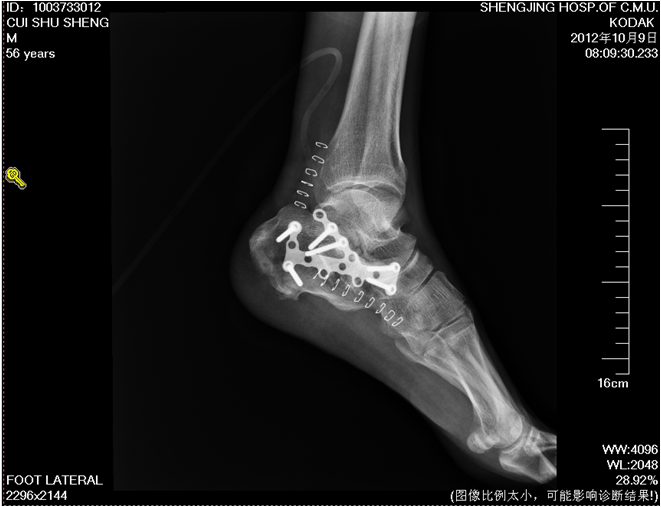

术后复查X线片示骨折复位良好,内固定在位且牢靠。根据骨伤科三期辨证理论,早期因瘀血停滞影响骨痂生长,故以活血化瘀,消肿止痛为主,应用桃红四物汤。术后证属肝肾亏虚,气血不足,治以补益肝肾,补气养血,应用愈骨胶囊等药物促进骨折愈合。术后嘱患者继续石膏托外固定,注意陪护,3月内扶双拐、按指导患肢不负重功能锻炼;休息3个月,加强营养,促进骨折愈合;继续中药应用,促进骨折愈合;定期复查,(1月、3月、6月);不适随诊。 本病例中医药应用结合手术复位,早期将骨折复位,中医药早期应用活血化瘀、消肿止痛,可迅速缓解患者症状。中医药中后期应用可促进骨折愈合,加快术后恢复,可使患者获得满意的术后疗效。